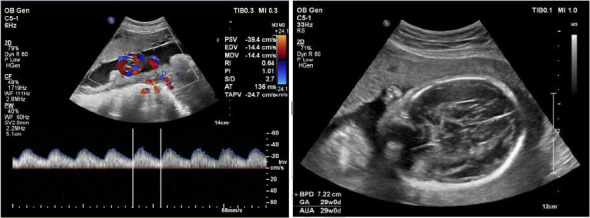

背景:妊娠期垂体神经内分泌肿瘤(pitNETs)的治疗具有挑战性。多学科团队(MDT)的参与有利于协同决策。然而,这方面还没有得到很好的记录。我们提供了妊娠期pitNETs的病例,并总结了我们在mdt指导下的治疗经验。方法:我们进行了一项回顾性研究,纳入了1995年3月至2024年7月期间在我们研究所治疗的所有妊娠pitNETs患者。结果:索引期间,121例pitNETs患者在妊娠期间来我院就诊,其中111例接受保守治疗,10例因进行性视力缺损等症状行手术治疗。纳入手术病例的年龄为33岁,手术时的妊娠期为13至36周(妊娠早期1周,妊娠中期4周,妊娠晚期5周)。在切除的肿瘤中,6例无功能,另外4例有功能(1例乳营养型,1例生长营养型,1例甲状腺功能)。所有手术病例均在神经外科、内分泌科、眼科、产科、儿科和麻醉科医生的指导下接受mdt治疗,所有患者的肿瘤全部切除,视力改善,分娩成功。结论:MDT指导下的妊娠期pitNETs治疗是必要的。对于症状迅速恶化的患者,手术切除肿瘤是必要的。全身麻醉下经蝶窦手术对妊娠期pitNETs患者是安全的。

Background: Management of pituitary neuroendocrine tumors (pitNETs) during pregnancy is challenging. Involvement of the multidisciplinary team (MDT) may benefit the collaborative decision-making. However, this aspect has not been well documented. We provided cases with pitNETs during pregnancy and summarized our experience on the MDT-guided management. Methods: We performed a retrospective study enrolling all pregnant patients with pitNETs treated at our institute between March 1995 and July 2024. Results: During the indexed period, 121 patients with pitNETs consulted our institute during pregnancy, with 111 of them being treated conservatively and 10 undergoing surgery due to progressive visual defect and other symptoms. The age of the included surgical cases was 33 years, and the gestational session at surgery ranged from 13 to 36 weeks (1 in the first trimester, 4 in the second, and 5 in the third). Of the resected tumors, six were nonfunctioning and the other four were functioning (1 lactotroph, 1 somatotroph, and 1 thyrotroph). All surgical cases received MDT-guided management by physicians from neurosurgery, endocrinology, ophthalmology, obstetrics, pediatrics, and anesthesiology, leading to gross total tumor resection, improved visual acuity, and successful delivery in all patients. Conclusion: MDT guided management is essential for pitNETs during pregnancy. Surgical tumor resection is necessary for patients whose symptoms deteriorate rapidly. Transsphenoidal operation under general anesthesia is safe for pregnant patients with pitNETs.